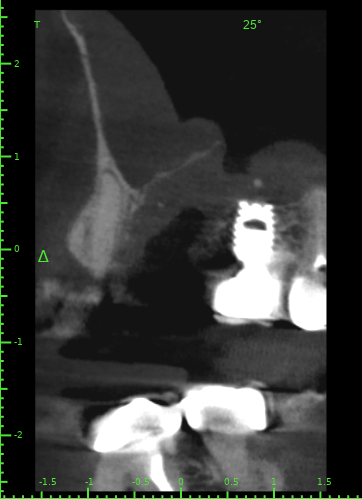

Atcotr Опубликовано 18 июля, 2024 Автор Поделиться Опубликовано 18 июля, 2024 @Женька @red_butler КТ сделано на 17-й день после удаления зуба. Не могли бы вы его посмотреть? Есть ли по вашему мнению свищ или признаки его формирования? Есть ли угроза для 27го импланта? Слизистая в гайморовой пазухе была опухшая задолго до удаления, это не новый процесс. КТ находится по ссылке: https://1drv.ms/f/s!AptB3I-32KWekuk4OkRq7Q6cdU7XcA?e=v69OYx Беспокоит чувство заложенности носа и уха слева после приёма любых жидкостей. Лечащий врач сказал, что небольшие перфорации в 95% случаев зарастают самостоятельно, назначил антибиотик и псевдоэфедрин и следующий приём через месяц. Спасибо за помощь. Ссылка на комментарий

Женька Опубликовано 19 июля, 2024 Поделиться Опубликовано 19 июля, 2024 Материала я, конечно, тут не особо вижу. Возможно он был, но весь вымылся. Перфорация действительно есть. Я бы ждал сейчас заживления и после оценивал формирование сообщения с пазухой. Снимок всю пазуху не вмещает, что там выше возле соустья неизвестно. Ухо, от ситуации на снимке, болеть вряд ли может на мой взгляд. Ссылка на комментарий